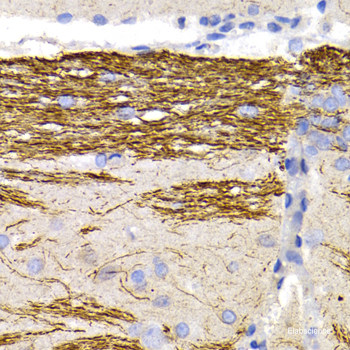

Neurofilaments are type IV intermediate filament heteropolymers composed of light, medium, and heavy chains. Neurofilaments comprise the axoskeleton and they functionally maintain the neuronal caliber. They may also play a role in intracellular transport to axons and dendrites. This gene encodes the light chain neurofilament protein. Mutations in this gene cause Charcot-Marie-Tooth disease types 1F (CMT1F) and 2E (CMT2E), disorders of the peripheral nervous system that are characterized by distinct neuropathies. A pseudogene has been identified on chromosome Y. Protein function: Neurofilaments usually contain three intermediate filament proteins: L, M, and H which are involved in the maintenance of neuronal caliber. [The UniProt Consortium]